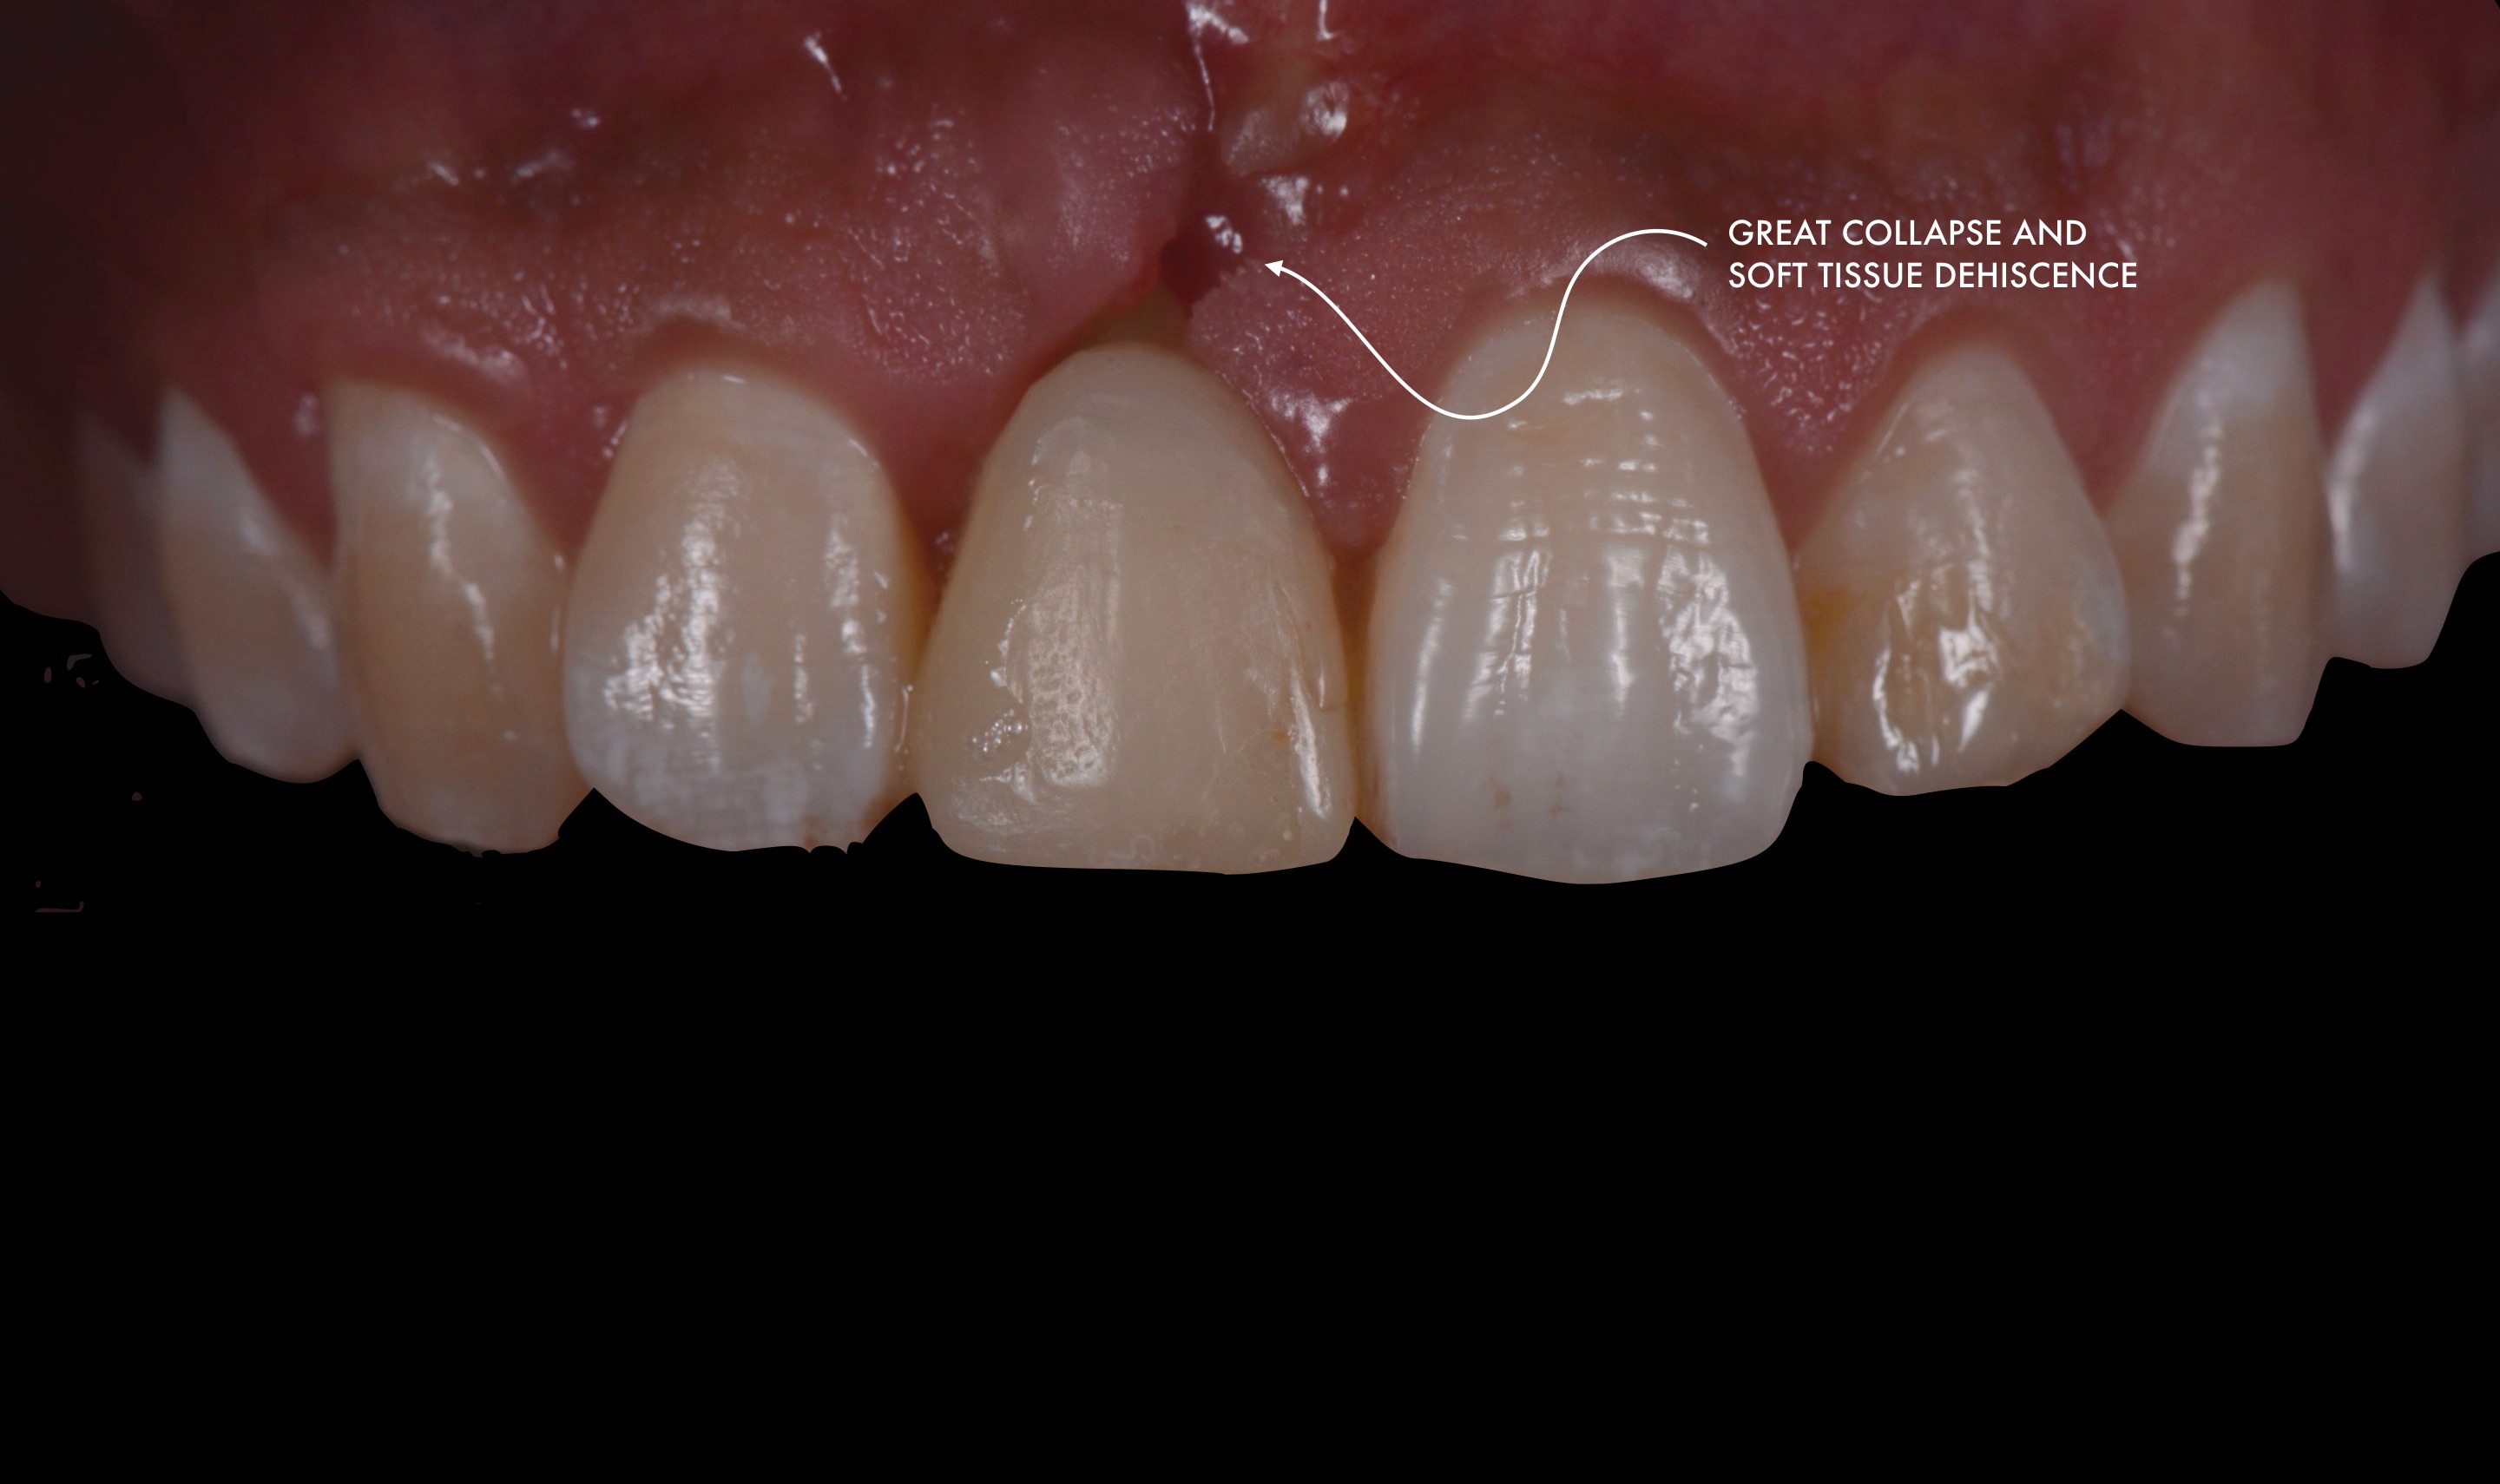

(PDF) “VERTICAL MIDCRESTAL INCISION” FLAP DESIGN IN SECOND STAGE Dental Implant Esthetic Zone immediate implant placement and provisionalization in the esthetic zone. surgical placement of dental implants in the anterior zone requires careful treatment planning, particularly in terms of fixture selection. Objectively, the esthetic zone was defined as any dentoalveolar segment that is visible upon. Treatment planning of implants in posterior. Implant therapy in the aesthetic zone: This technique report details. Dental Implant Esthetic Zone.